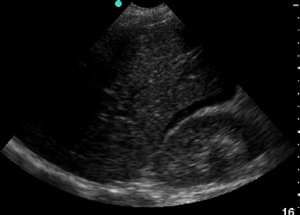

fig-4-free-fluid-in-morrisons-pouch-consistent-with-hemoperitoneum-in-a-trauma